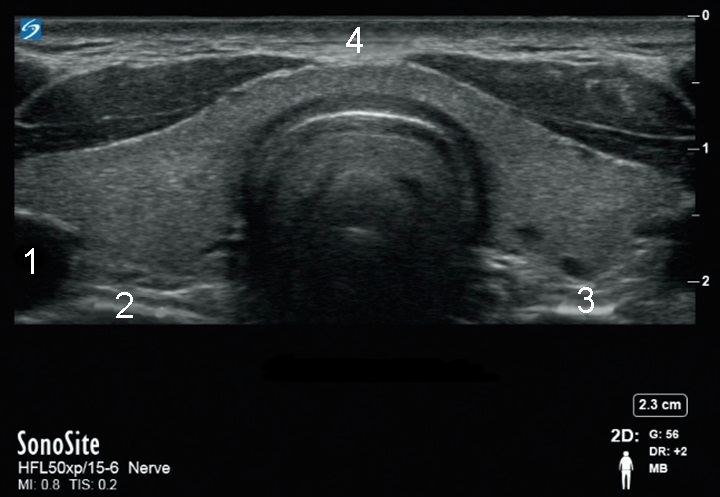

Transversale Aufnahme der Schilddrüse mit X-Porte

Rechter Lappen

Linker Lappen

Isthmus